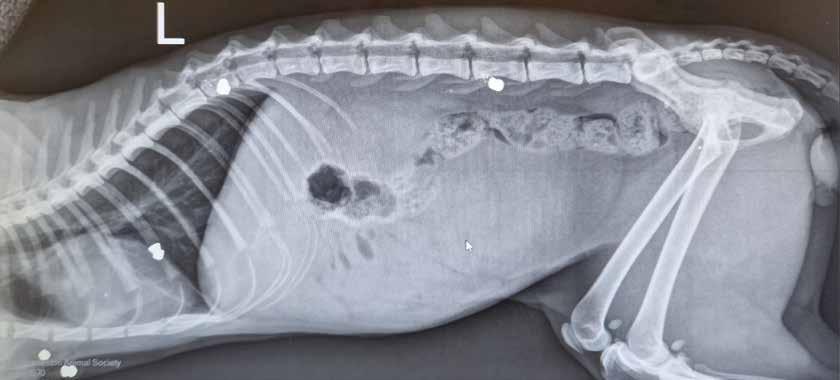

Back at his home, Johnny had two eight-

year-old Cane Corsos, Gina and Luca. At 73 and 120 pounds, these gentle giants were alone and suffering from age-related arthritis and skin issues. Luca also had a massive growth on his hip. As they sat alone in Johnny’s apartment, they had no idea that their lives had just been turned upside down.

As their human fought for his life, both Luca and Gina received daily care from Stephanie and Tyson, but they soon realized that they would need long-term care and turned to Charleston Animal Society for help. It didn’t take long for our staff to fall in love with these sweet old

souls. Their big, kind eyes and soft, gray faces melt the hearts of everyone who met them. Our veterinary team saw to all of their medical needs, and our animal care staff made sure they had plenty of exercise, lots of treats, and tons of love.